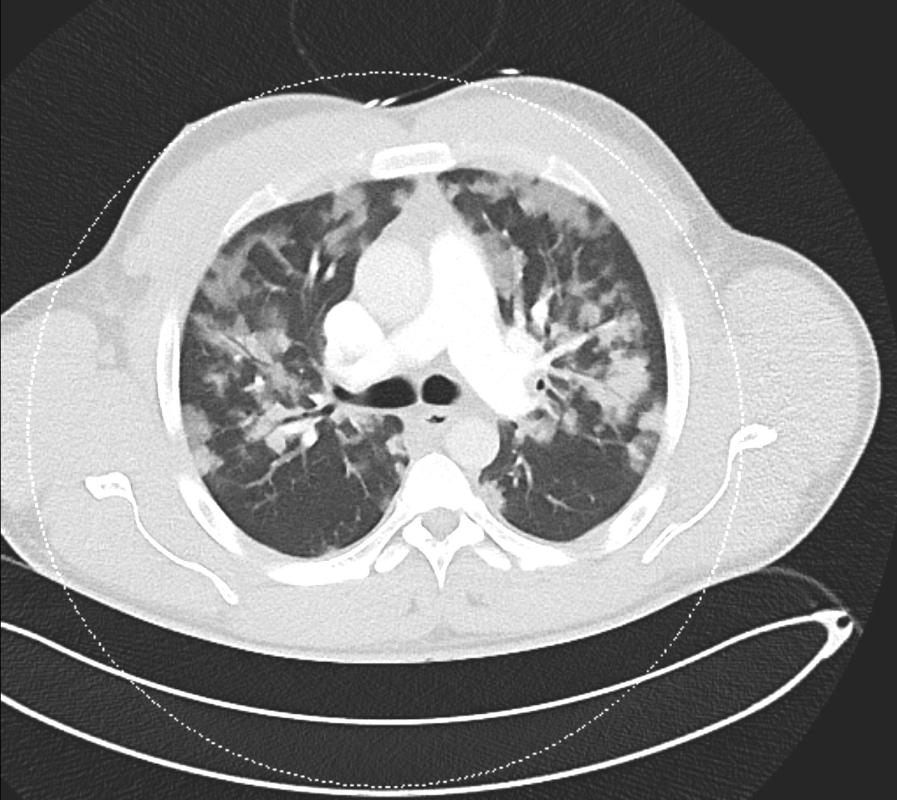

CT扫描排除了肺栓塞,但显示出心脏增大,右心室扩张,表明存在肺阻力。肺部所有叶段均表现出弥漫性浸润性病变,与肺水肿和潜在感染一致。磨玻璃样影进展到实变提示肺泡损伤和微出血,增加了急性呼吸窘迫综合征(ARDS)的可能性。

7e08d58355fd7bb649ffce539800f4c6.jpg